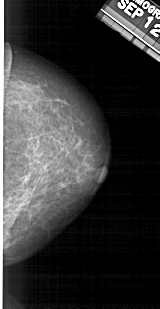

A_1637_1.RIGHT_MLO

RIGHT_CC LINES 4621 PIXELS_PER_LINE 2386 BITS_PER_PIXEL 12 RESOLUTION 43.5 NON_OVERLAY

RIGHT_MLO LINES 5491 PIXELS_PER_LINE 2536 BITS_PER_PIXEL 12 RESOLUTION 43.5 NON_OVERLAY